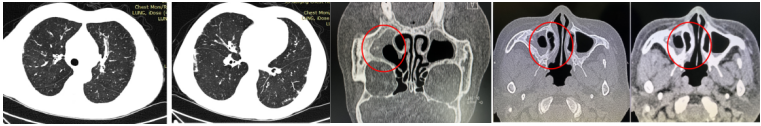

患者男性,63岁,退休,既往有糖尿病史20余年,因“发作性胸闷1月”于2019年1月16日入院。患者1月来发作性胸闷2次,伴有咳嗽,大量黄脓痰,活动后气喘,第二次发病时伴发热,抗生素治疗效不显,冠状动脉造影排除心肌梗死,血气分析提示低氧血症。血嗜酸性粒细胞计数及比例正常。血自身抗体组合:抗SM抗体、抗PCNA抗体弱阳性。胸部CT示胸膜下少许斑片影。鼻窦CT示上颌窦少许积液(图3)

图3  病例2就诊时胸部CT及鼻窦CT

请风湿科会诊排除自身免疫病,予甲泼尼龙80 mg qd,气喘稍好转。行气管镜检查送检灌洗液G试验153.0 pg/ml,GM试验0.99。加用伏立康唑抗真菌治疗后当晚症状好转,1周后症状消失,复查胸部CT,病灶吸收(图4)。为何伏立康唑的“平喘”疗效会如此迅速?因为该患者的诊断是联合气道烟曲霉病——真菌敏感性重症哮喘+变应性真菌性鼻/鼻窦炎。

图4  病例2出院时胸部CT